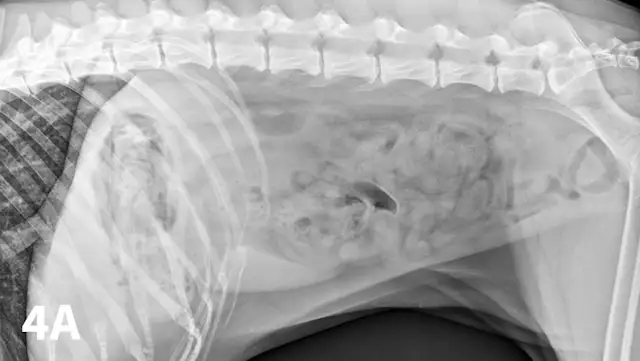

Radiographic features of small intestinal mechanical obstruction depend on its completeness, location, and duration.2 Whereas metallic FBs or those with mineral content are easily recognized within the GI lumen (Figure 1), nonmineralized, nonmetallic objects (eg, cloth) within the GI tract are more difficult to identify (Figure 2). Some may be recognized by their geometric shape. The most consistent sign of mechanical obstruction is variable dilation of intestinal loops proximal (orad) to the obstruction (described as a mixed population of small intestine; Figure 2). Determination of small intestinal diameter can be made by comparing it to the L5 vertebral body height in dogs.3 Values greater than 1.6 are suggestive of obstruction (Figure 2A). In cats, a ratio of the maximum small intestinal diameter to vertebral end plate height of L2 greater than 4 indicates a high likelihood of intestinal obstruction.4

Qualitative assessment of intestinal size by experienced clinicians may be as accurate in determining the presence of mechanical obstruction as calculation of ratios. Obstructed intestine usually contains fluid and gas; however, if the obstruction is orad, reflux into the stomach can occur and limited intestinal distension may be apparent. More distal (aborad) or more complete obstruction leads to greater dilation. Stacking of intestinal loops occurs with more severe dilation as segments become increasingly crowded in a relatively smaller space (Figure 2B).

Right lateral (A) and VD (B) abdominal radiographs of a Labrador retriever with an obstructive ileus. A FB (sock) is present within a dilated small intestinal loop in the right caudoventral abdomen (arrows). The dashed lines outline a fluid-filled loop measuring 2.7 cm and a gas-filled loop measuring 2.4 cm, compared to the height of L5 (Asolid line, 1.1 cm);  the resulting ratios of 2.4 and 2.2, respectively, are much greater than the upper limit of 1.6 for normal small intestine to L5 height ratio. Several stacked gas-filled loops of small intestine are present in the left midabdomen (B).